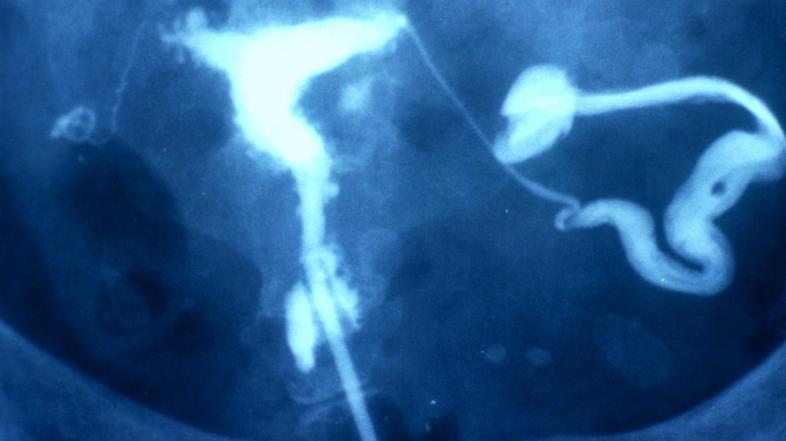

Endometrioza Profimedias

Endometrioza močno vpliva na kakovost življenja vsake desete ženske, a kljub temu sodi med najbolj nepojasnjene, napačno diagnosticirane in spregledane bolezni. O izkušnjah z boleznijo smo o našem portalu že pisali, lani je bilo v Sloveniji ustanovljeno in registrirano še civilno društvo Endozavest.

Endimetrioza Zdravje Boleča menstruacija je lahko znak bolezni